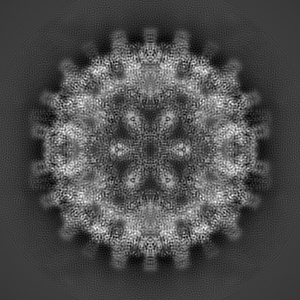

Hepatitis B core protein with low secretion phenotype (P5T) and bound GSLLGRMKGA

Conformational Plasticity of Hepatitis B Core Protein Spikes Promotes Peptide Binding Independent of the Secretion Phenotype.

Makbul C , Khayenko V , Maric HM , Bottcher B

(2021) Microorganisms , 9